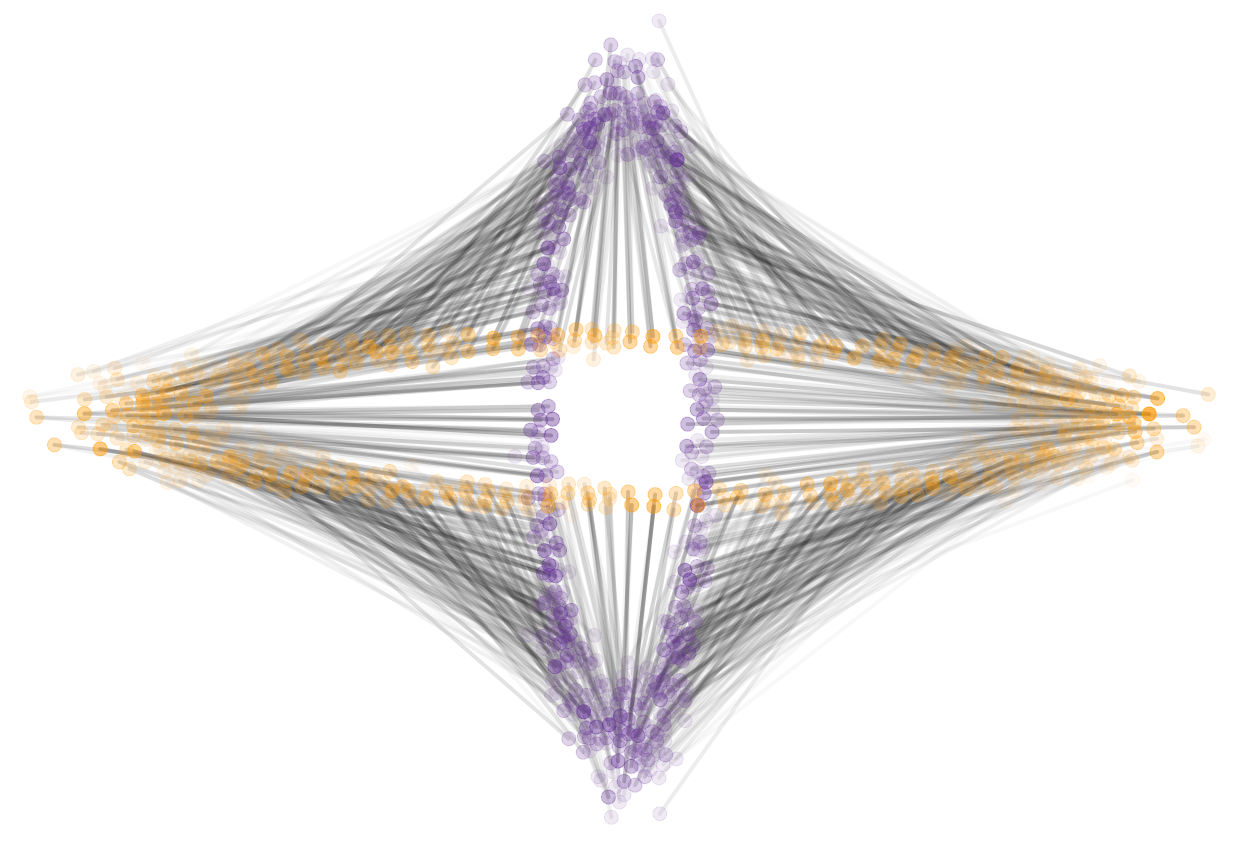

To solve for the optimal transport map between two 3D brain images we extract for each image a point cloud from the intensity volumes. Each point represents a voxel as a point in 3-dimensional space, the location of the voxel. The mass of the point is equal to the intensity value of the voxel, normalized to sum to one over all points. For illustration, Figure 9 shows a single slice extracted from the original volumes and optimal transport maps between the two slices. This 2D problem resulted in point set of approximately points.

|

|

| (a) | (b) |

|

|

| (c) | (d) |